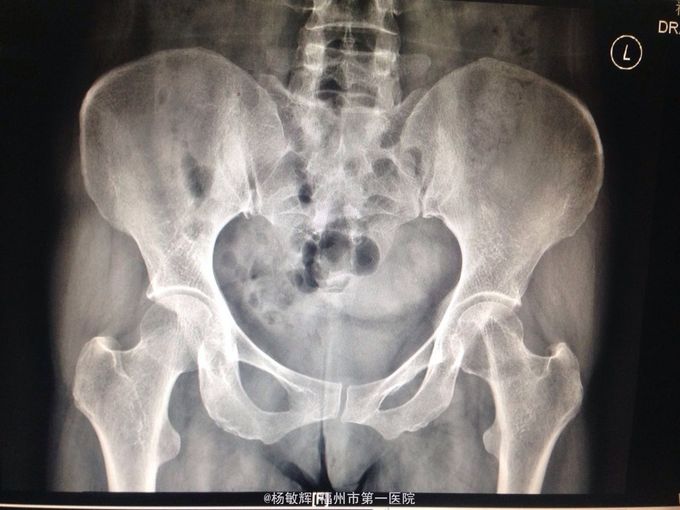

女性,48岁,以“左髋部疼痛伴活动受限2年”为主诉入院。缘于入院前2年无明显诱因出现左髋部疼痛不适,疼痛呈间歇刺痛,无向他处放射,伴左髋部活动受限,间歇性跛行,就诊当地医院查髋部X线提示:骨质破坏。MRI提示:左股骨头异常信号。当地医院诊断股骨头占位,未予以特殊处理,2周前疼痛加剧,就诊我院,查左髋部MRI提示:左髋部占位,骨巨细胞瘤可能性大。入院后于穿刺活检送病理,病理结果:左股骨头骨巨细胞瘤。拟:左股骨近段骨巨细胞瘤,收住院。

左股骨近段骨巨细胞瘤 入院后完善相关术前检查,未见明显手术禁忌症,行:左股骨近段占位切除+人工髋关节置换术